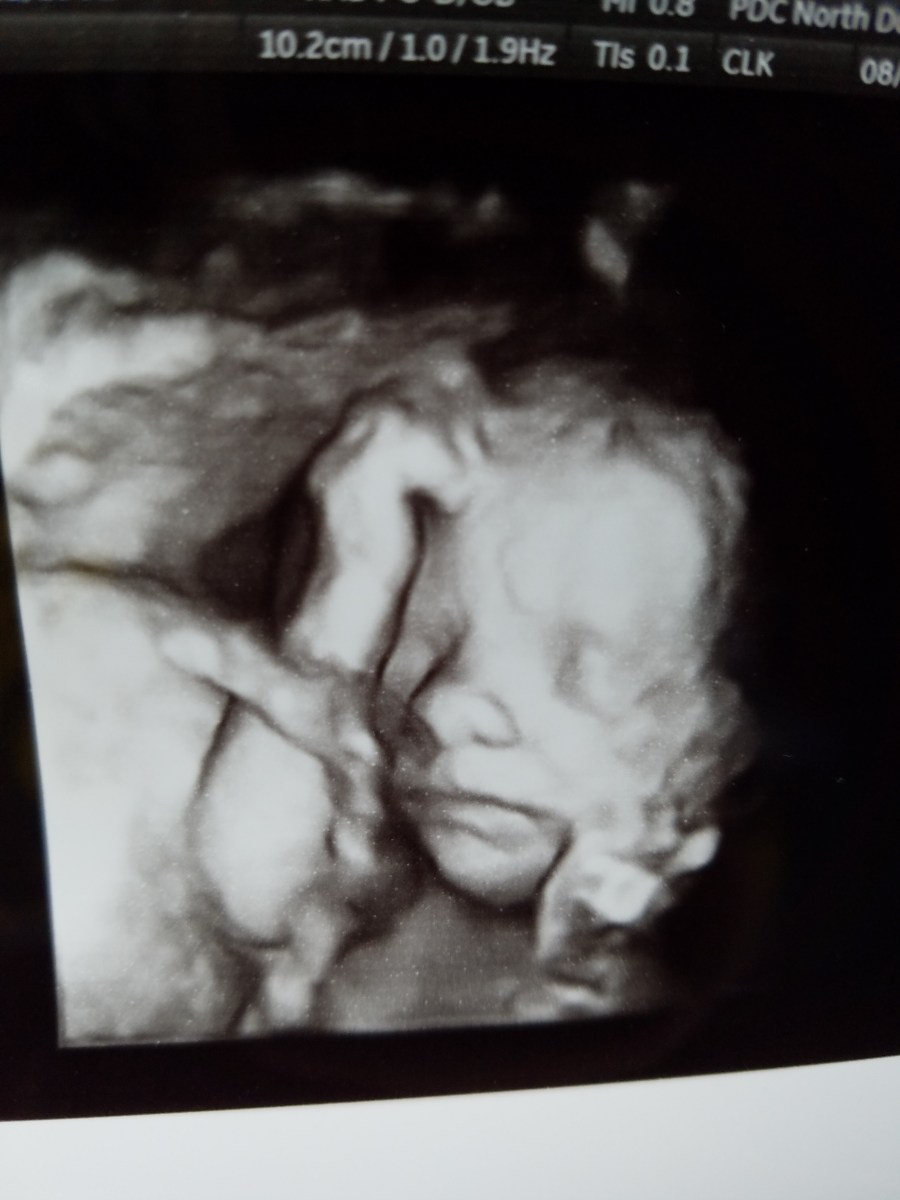

20170824_161624 Published August 25, 2017 at 3024 × 4032 in Lucky Bean In Utero « Previous Next » Like Loading...